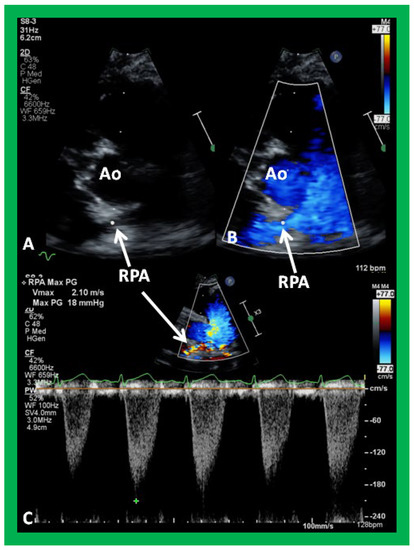

Figure 34. Selected video frames from parasternal short axis view demonstrating stenosis of the right pulmonary artery (RPA) by two dimensional (A) and color (B) and pulsed (C) Doppler imaging. Doppler calculated gradient was 18 mmHg (C). Ao, aorta.